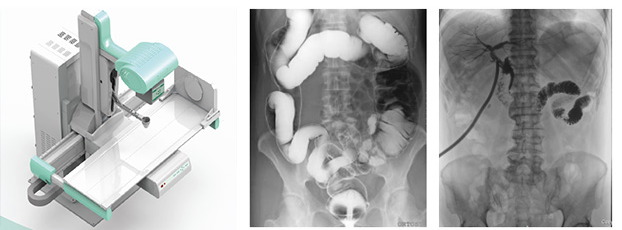

DR的全稱是數(shù)字X線攝影設(shè)備,是采用X線探測(cè)器將X線影像轉(zhuǎn)換成電信號(hào),再轉(zhuǎn)化為數(shù)字影像;也可通過(guò)X-TVX線照片獲得模擬影像,再轉(zhuǎn)換成數(shù)字影像。隨著DR技術(shù)的發(fā)展,近年來(lái)更是出現(xiàn)了動(dòng)態(tài)DR,大大降低了漏診誤診率。然而,也有不少基層醫(yī)院反應(yīng),買(mǎi)到了假動(dòng)態(tài)DR。接下來(lái)小編就來(lái)科普一下什么才是真正的動(dòng)態(tài)DR

動(dòng)態(tài)DR可以理解為一種不同角度觀察器官運(yùn)動(dòng)的X光視頻。常規(guī)的靜態(tài)DR更多的顯示的是器官的投影像,單一角度單一時(shí)間點(diǎn)很難發(fā)現(xiàn)細(xì)微病灶。而真正的動(dòng)態(tài)DR可以從不同的角度、時(shí)間來(lái)觀察器官的運(yùn)動(dòng),診斷準(zhǔn)確率會(huì)大大提升。動(dòng)態(tài)DR的多角度檢查,其視覺(jué)效果上有點(diǎn)類似于CT。

從功能上來(lái)說(shuō),真正的動(dòng)態(tài)DR是一款能夠數(shù)字拍片、數(shù)字透視、數(shù)字造影的多功能DR

從技術(shù)上來(lái)說(shuō),真正的動(dòng)態(tài)DR是使用多功能動(dòng)態(tài)數(shù)字化探測(cè)器成像的直接數(shù)字化X射線攝影系。

從臨床上來(lái)說(shuō),真正的動(dòng)態(tài)DR具有大幅面(17inch×17inch)高清拍片、大幅面(17inch×17inch)透視、視頻實(shí)時(shí)保存回放、可視化造影、毫秒級(jí)點(diǎn)片等基礎(chǔ)功能,以及斷層融合、數(shù)字減影等延展性功能。

只有同時(shí)滿足功能、技術(shù)和臨床三方面標(biāo)準(zhǔn)的動(dòng)態(tài)DR,才能稱得上是真正的動(dòng)態(tài)DR。好了,小編科普就到這里??赐赀@文章,你有了解到你想知道的內(nèi)容嗎?如果你想了解更多,歡迎關(guān)注“普朗醫(yī)療器械網(wǎng)”,我們會(huì)定期的更新一些新的內(nèi)容供大家瀏覽閱讀。